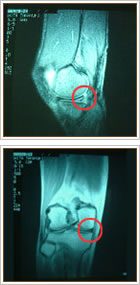

腰骨の変形や靱帯の肥厚、ヘルニアなどにより、腰の神経が圧迫され腰痛、足の痛みやしびれなどが出現し長歩きが困難になります。足のしびれの原因で一番多いのが腰椎の変形によるものです。50歳以降に発症します。

※MRI写真を見ると、神経が周囲から圧迫されて、赤い矢印のところで細くなっているのが分かります。 |

腰骨のクッションである椎間板が靭帯を破り後方に突出して腰の神経を圧迫すると腰痛や脚の痛み、シビレが出てきます。

※MRI写真を見ると、赤い矢印の黒く抜けた部分がヘルニアで、神経を圧迫しているのが分かります。 |